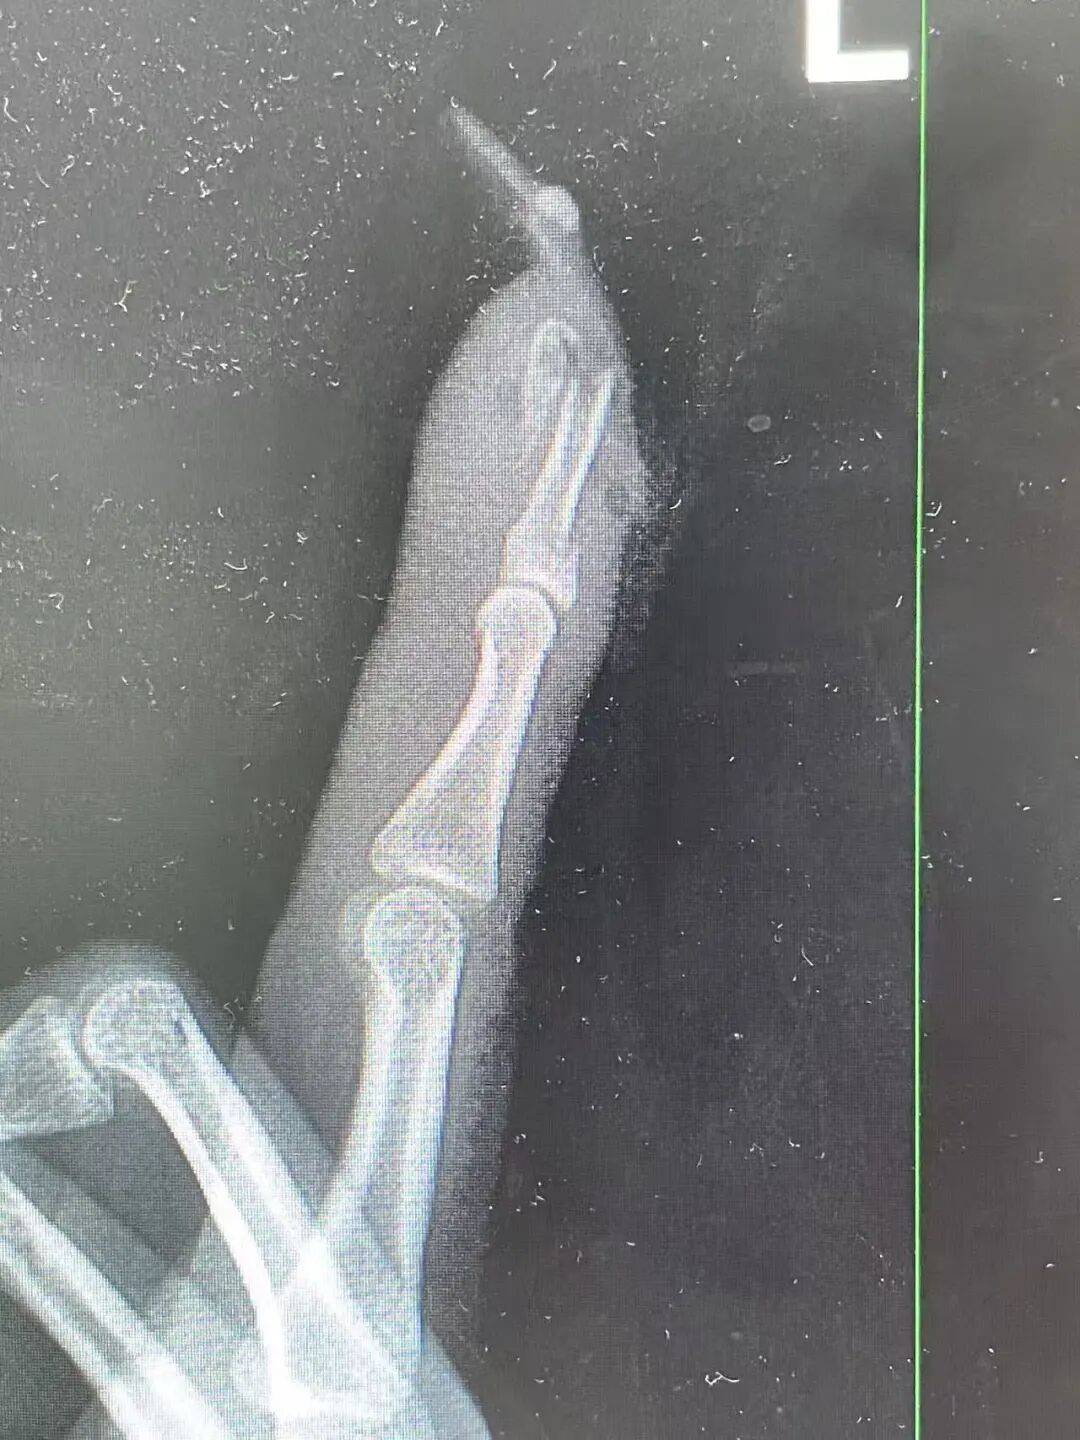

“食指指骨骨折,甲床破裂。”接诊的骨科医生曹立检查后发现王女士指甲断裂,部分甲床外露,需要手术修复。曹医生立刻为王女士进行指骨骨折闭合复位内固定术,术后恢复良好。曹医生表示,如果没有美甲,伤害不会这么严重。